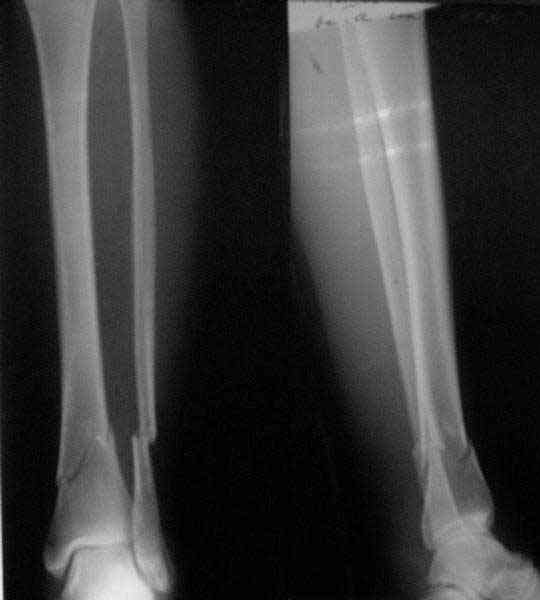

Re: Проксимальный и дистальный переломы tibia

Myles Clough 18 Май 2006, 15:32

From the Xrays it seems as though the proximal fracture is relatively undisplaced. I thought that Poller screws were mostly used to prevent displacement of the fracture while the nail was being inserted. In this case I would think that you could hold the reduction temporarily either with a clamp, crossed K wires or a lag screw. Then insert the nail and place a proximal blocking screw only if you need to. Will the proximal locking screws fix the proximal fragment? Are you going to fix the fibula?

A typical case is attached, also an image with intra-op reduction obtained by a small wire distractor, in the moment of insertion a Poller wire in AP direction. Fixation by a SIGN nail. Despite the fibula was not fixed healing was obtained with the unchanged alignment.